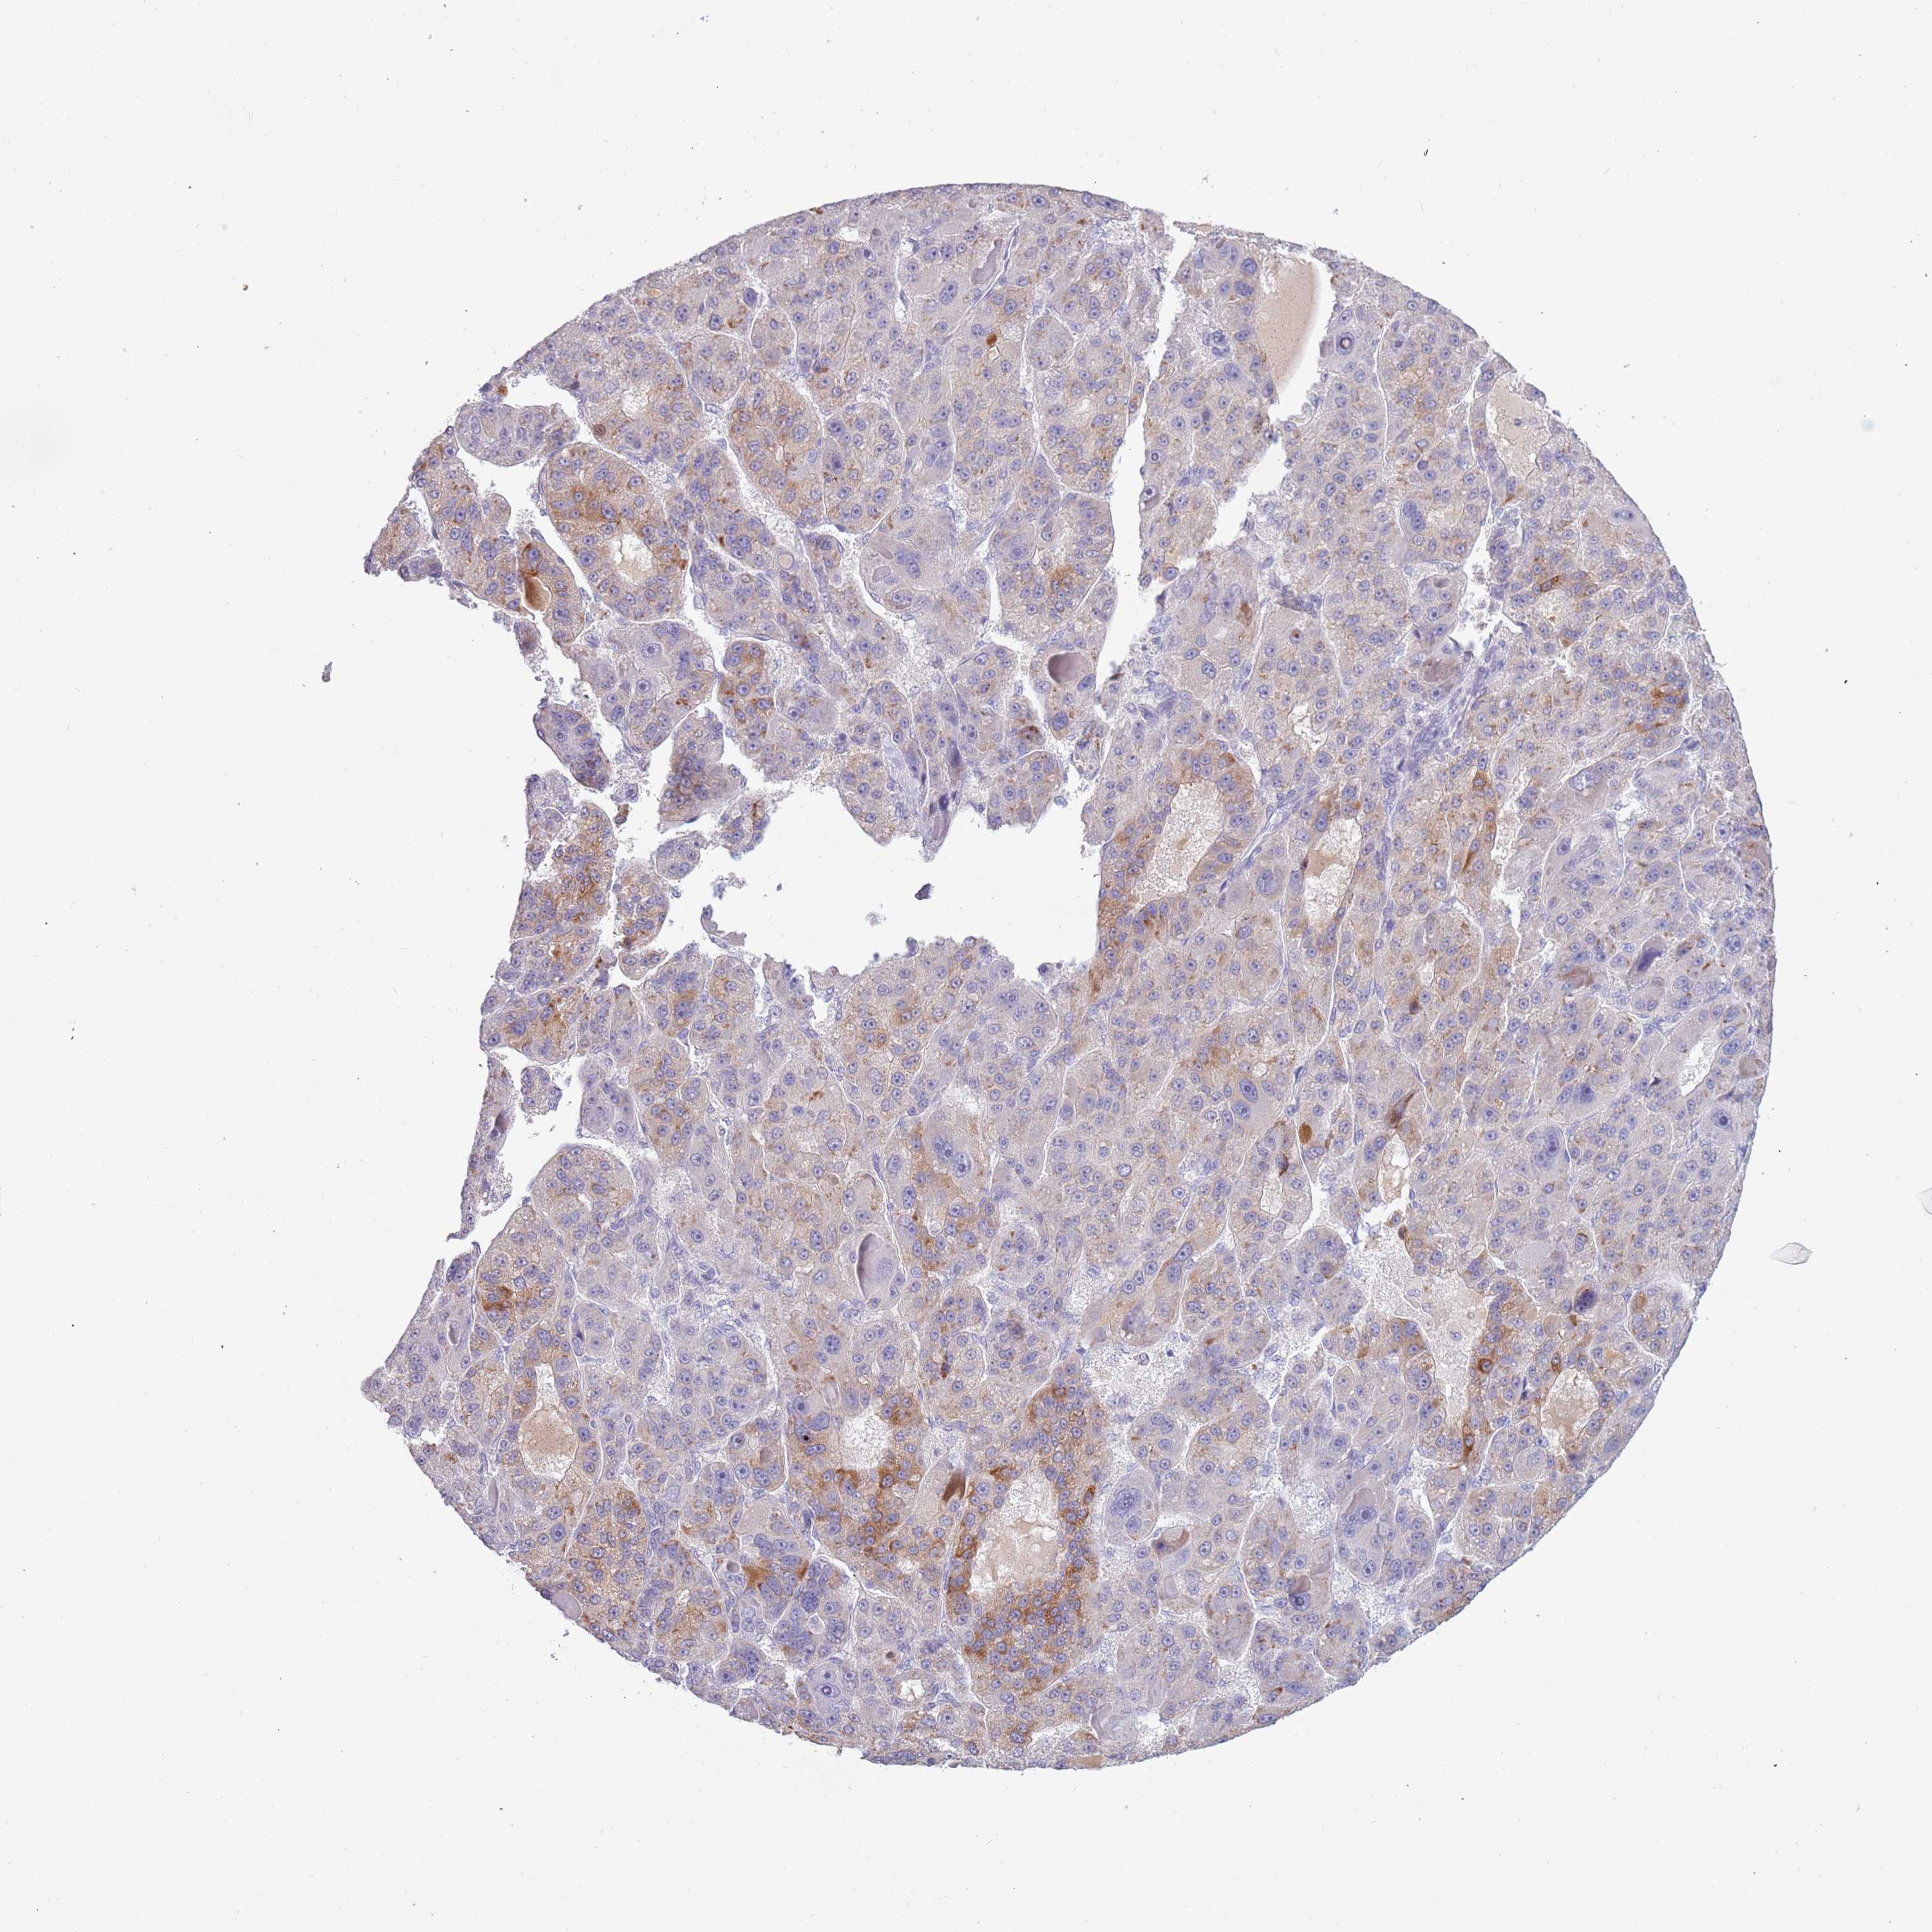

LIVER CANCER - Protein expressioni

A mouse-over function shows sample information and annotation data. Click on an image to view it in a full screen mode. Samples can be filtered based on level of antibody staining by selecting one or several of the following categories: high, medium, low and not detected. The assay and annotation is described here.

Note that samples used for immunohistochemistry by the Human Protein Atlas do not correspond to samples in the TCGA dataset.

Antibody stainingi

Antibody staining in the annotated cell types in the current human tissue is reported as not detected, low, medium, or high, based on conventional immunohistochemistry profiling in selected tissues. This score is based on the combination of the staining intensity and fraction of stained cells.

Each image is clickable and will lead to virtual microscopy that enables deeper exploration of all samples and also displays staining intensity scores, fraction scores and subcellular localization as well as patient and tissue information for each sample.

Antibody HPA047154

Staining

High

Medium

Low

Not detected

Intensity

Strong

Moderate

Weak

Negative

Quantity

>75%

75%-25%

<25%

None

Location

Nuclear

Cytoplasmic/membranous

Cytoplasmic/membranous,nuclear

Cholangiocarcinoma

Carcinoma, Hepatocellular, NOS